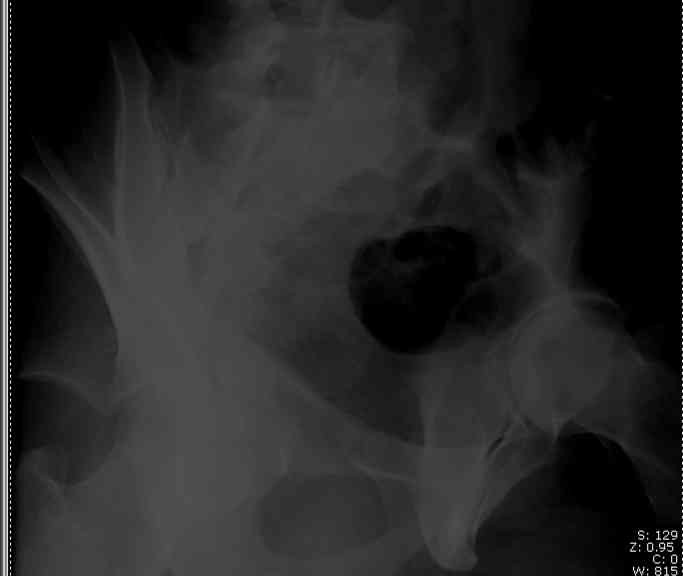

-Sciatic Nerve

The Farabeuf compresses the posterior column limb and this maneuver usually distracts the anterior column component... just like you'd expect it to... the clamp screws are either quite short, directed away from the joint worsening the ACol distraction, or mistakenly inserted into the

joint. The clamp also contacts most sciatic nerves while it's in and unprotected.

Screw Fixation

-AC Screw

-PC Screw

For Alex... here are some cannulated and 7mm screws for you... notice the fracture malreduction as indicated by the head subluxation on both views...this was a percutaneous technique without open reduction... I don¹t like it but there it is... the fixation technique is not at fault, because there was no open reduction of the fracture... but let¹s not get in to all that.